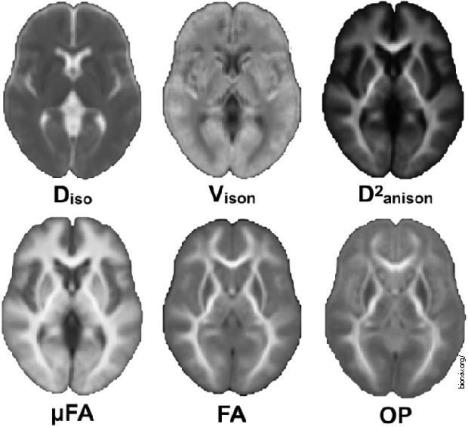

Utvrđeno je da se mikrostruktura bele mase - mreže neuronskih vlakana koje prenose informacije između regiona sive mase - menja sa hormonskim promenama, uključujući uticaj koji nose pubertet, upotreba oralne kontracepcije, hormonske terapije...

Tim stručnjaka je obavio snimanje uz magnetnu rezonancusvojih ispitanika tokom tri menstrualne faze: menstruacije, ovulacije i srednje lutealne. U vreme svakog od ovih skeniranja, istraživači su takođe merili nivoe hormona učesnika.

Rezultati istraživanja su pokazali da se, kako hormoni fluktuiraju, tako se menjaju i zapremine sive i bele mase, kao i zapremina cerebrospinalne tečnosti.

Konkretno, neposredno pre ovulacije, kada se povećavaju nivoi hormoni 17 beta-estradiola i luteinizirajućeg hormona, mozak učesnica pokazao je promene bele mase što sugeriše brži prenos informacija.